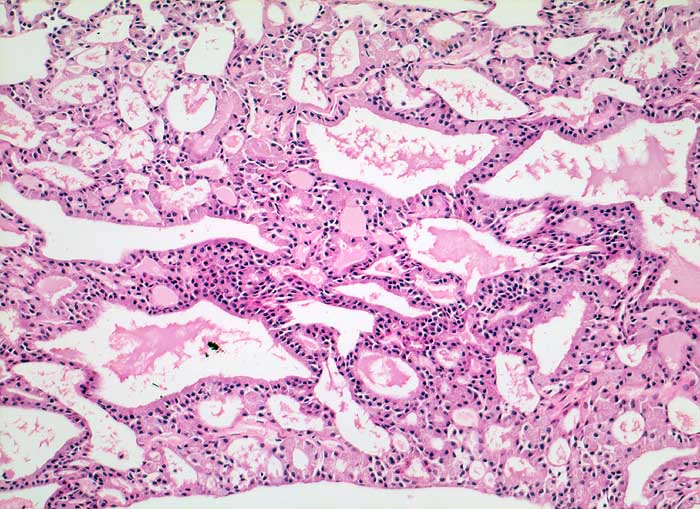

Azinuszellkarzinom der Glandula Parotis

Die zytologische Diagnose des Azinuszellkarzinoms basiert auf dem Nachweis von Azinuszellen bei gleichzeitigem Fehlen von Gangstrukturen. Die Tumorzellen gleichen normalen serösen Azinuszellen. Zytoplasma ist reichlich vorhanden und variiert von schaumig bis grobgranulär. Degranulierte Zellen erscheinen schaumig, Zellen mit dichtgepackten Granula gleichen Onkozyten. Die Granula der Onkozyten sind aber feiner. Die Tumorzellkerne sind meist ziemlich wenig atypisch und monomorph. Das Chromatin variiert von fein bis mittelgrob. Intranukleäre Zytoplasmaeinschlüsse kommen vor. Die oft vorhandenen zahlreichen Nacktkerne müssen von ebenfalls oft vorhandenen Lymphozyten abgegrenzt werden. Die meist hoch differenzierten Tumoren können mit normaler Speicheldrüse verwechselt werden.